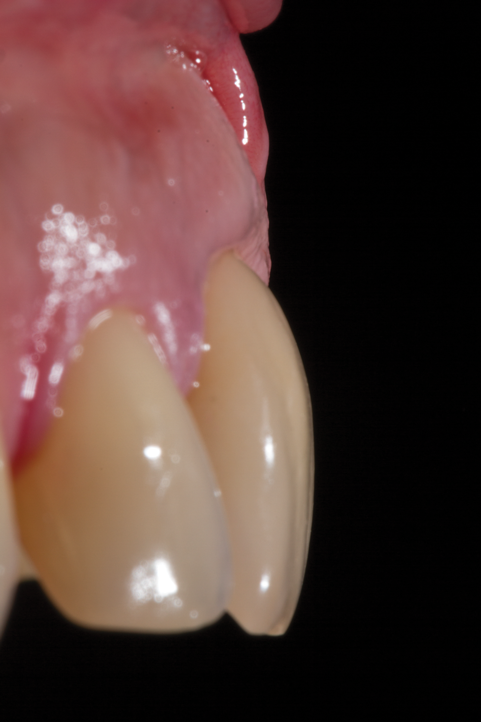

Fig 5. Preoperative clinical image of tooth No. 8 (1:1). A thin scalloped phenotype, prone to collapse upon removal of the tooth, was evident.

Figure 5